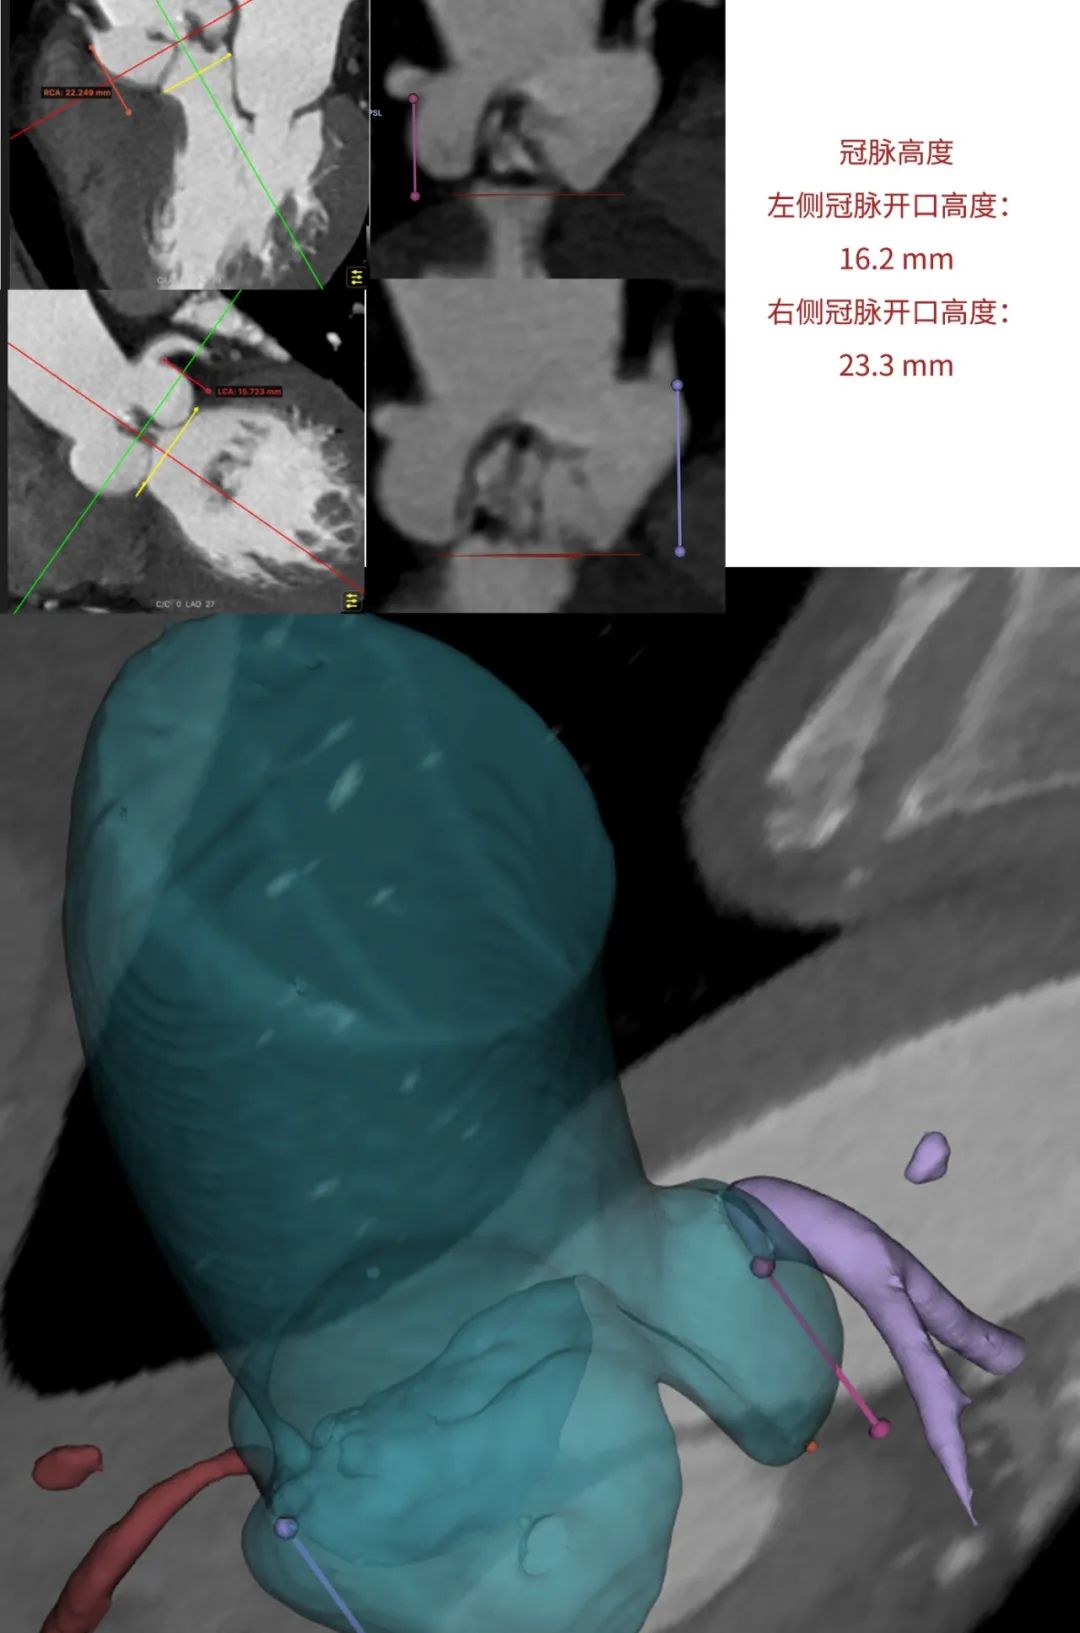

患者为68岁男性,因心悸胸闷入院。术前超声报告显示,患者为功能型二叶式主动脉瓣,右无融合钙化,主动脉瓣明显增厚钙化,瓣叶开放受限,主动脉瓣前向血流加速Vmax=4.2m/s,平均跨瓣压差36mmHg,有效开口面积0.7cm²,舒张期瓣口中度反流信号。

临床团队同时使用了基于医生手工描点的围术期影像评估软件和基于人工智能的瓣膜疾病围术期分析辅助决策软件进行术前影像学评估。

通过术前测量,对病例深入分析,结合人工智能术前分析辅助决策软件进行三维和二维图像融合,郭应强教授指出本例手术存在以下难点:

患者不到70岁,需要考虑远期冠脉保护。